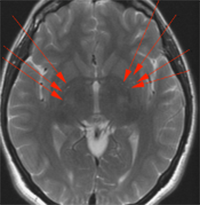

FIG 2. Lesiones isquémicas difusas de la sustancia blanca profunda.RM en un paciente con Enfermedad del Filum muestra numerosas lesiones isquémicas focales dentro de la sustancia blanca profunda hemisférica, los ganglios basales (flechas rojas), que desaparecieron tras la intervención.

Podemos suponer que la predisposición a otras lesiones cerebrales a raíz de la endotelitis puede agravar o aumentar las secuelas en los pacientes que padecen, a la vez, la COVID-19 y la Enfermedad del Filum.

Sabemos que esa predisposición inflamatoria cerebral de la Enfermedad del Filum, desaparece con el tratamiento quirúrgico propuesto para ella, por lo que puede ser recomendable su pronto diagnóstico y tratamiento adecuado.